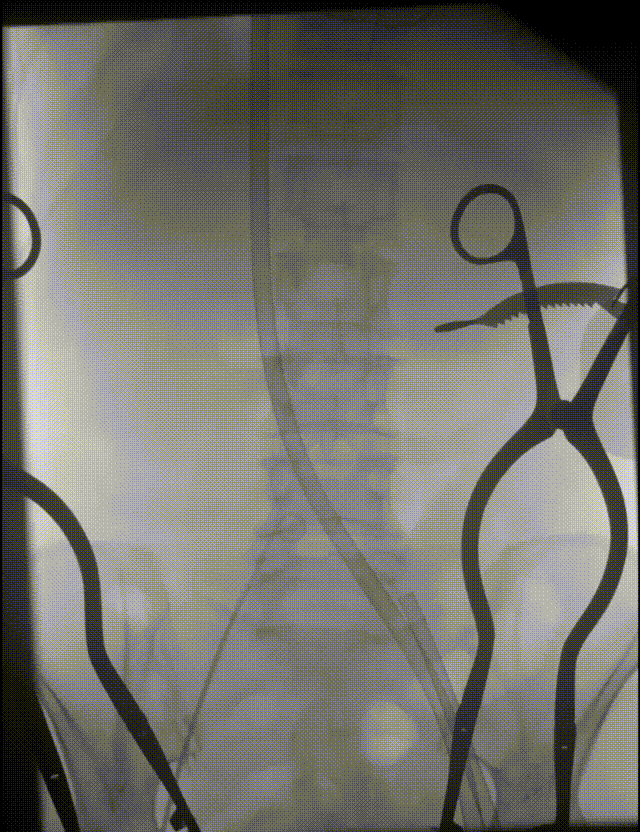

22mm球囊后扩,瓣膜形态改善,无明显瓣周漏

脱钩后,22mm球囊后扩,瓣膜形态改善

最终造影,无明显瓣周漏

弓部造影检查

无损伤

外周血管检查,无损伤